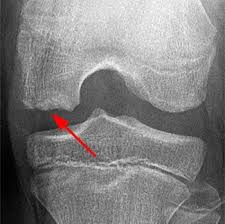

ऑस्टियोकॉन्ड्राइटिस डिस्केन्स का परीक्षण ? (Diagnosis of Osteochondritis dissecans)

जो व्यक्ति जोड़ में ओसीडी के लक्षणों का अनुभव करते हैं, उसे चिकित्सा की सलाह जरूर लेनी चाहिए। इसका जल्दी इलाज करवाने का मतलब है अधिक प्रभावी उपचार और जोखिम को कम करना। इसकी जांच के लिए सबसे पहले डॉक्टर शारीरिक जांच करेंगे और आपको अपने जोड़ों को अलग-अलग दिशाओं में मूवमेंट के लिए कहेंगे और साथ ही मरीज से उनके मेडिकल इतिहास, पारिवारिक इतिहास और जीवनशैली के बारे में पूछेंगे, जिसमें खेल गतिविधियाँ शामिल हैं। कुछ इमेजिंग परीक्षण हो सकते हैं, जैसे कि एक्स-रे (X-Ray), सीटी स्कैन (CT Scan), एमआरआई (MRI) स्कैन या अल्ट्रासाउंड (Ultrasound)। यह दिखा सकता है कि क्या कोई गलन है, या टिशू की मृत्यु। एक हड्डी स्कैन के लिए भी बोला जा सकता है। शुरुआती चरणों में, परीक्षण दिखाएगा कि कड़ी लचीली हड्डी मोटी हो रही है। बाद के चरणों में वह ढीले टुकड़े हो जाएंगे। शुरुआती चरणों को स्थिर माना जाता है, और इस चरण पर उपचार प्रभावी होने की अधिक संभावना होती है। इसमें गठिया, ऑस्टियोआर्थराइटिस (Osteoarthritis), हड्डी के अल्सर (Ulcer) और सेप्टिक गठिया शामिल हैं।